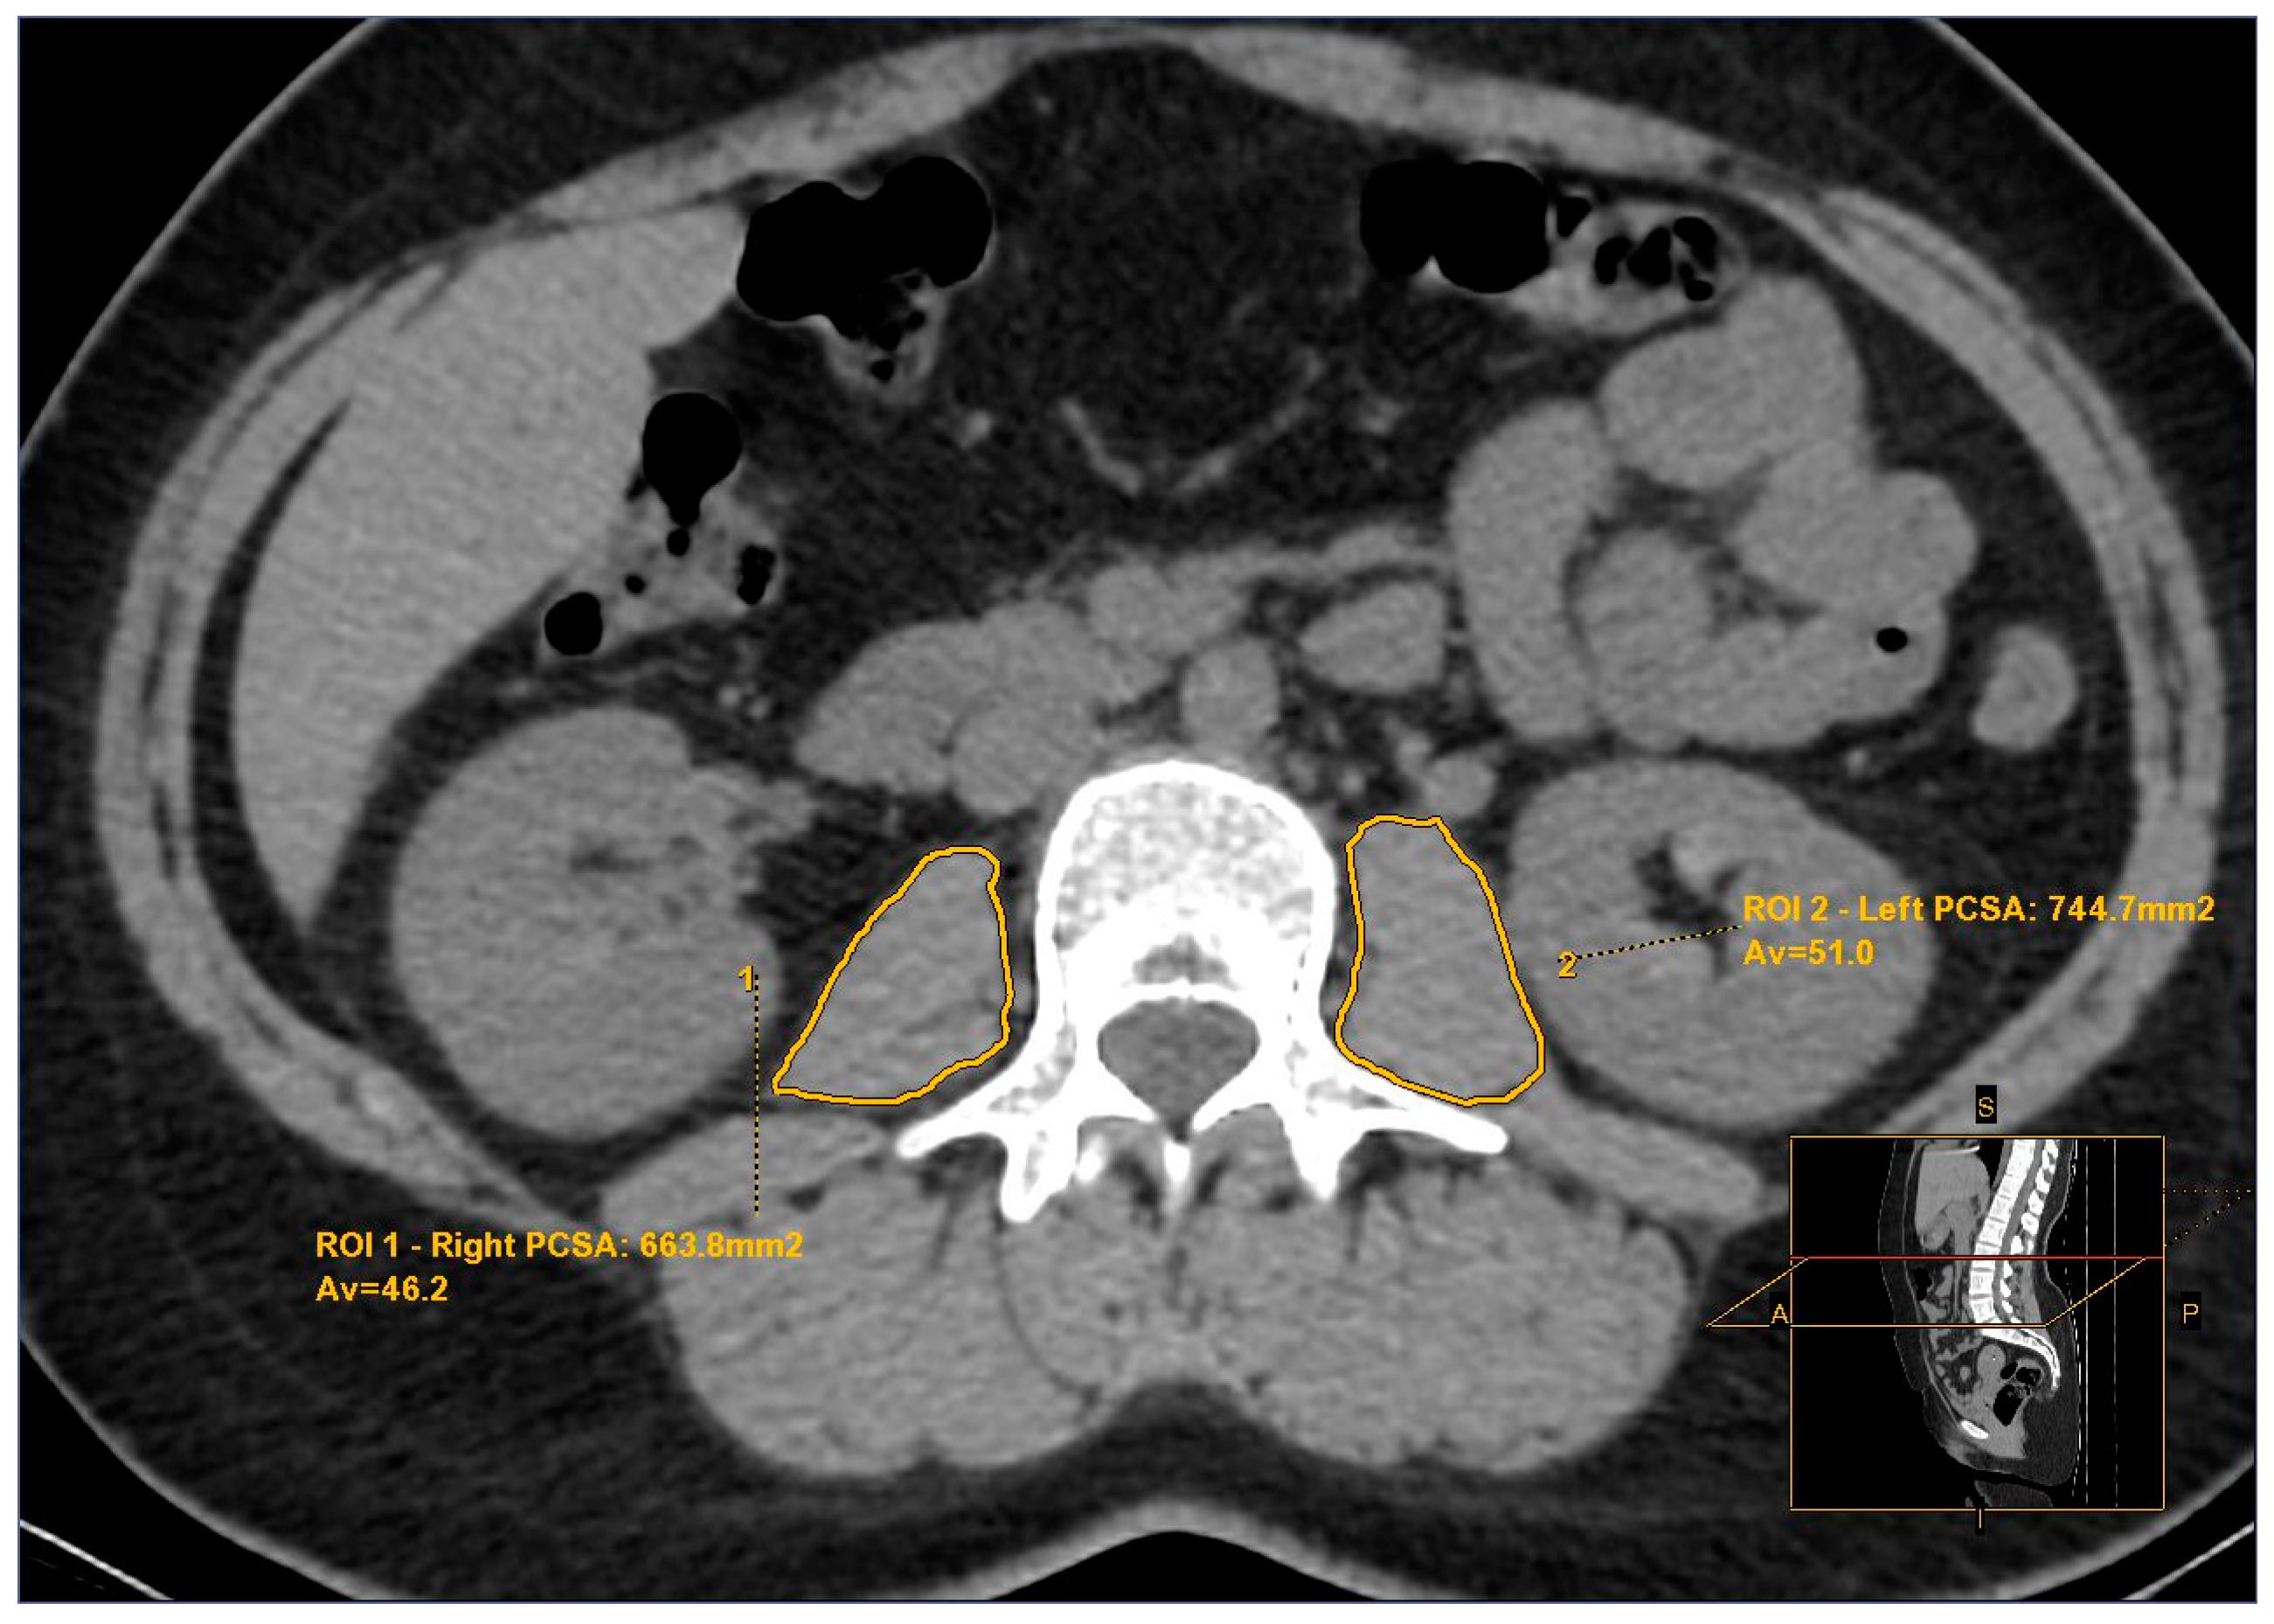

2.2. Psoas Muscle Assessment

- Gomez-Perez, S.L.; Haus, J.M.; Sheean, P.; Patel, B.; Mar, W.; Chaudhry, V.; McKeever, L.; Braunschweig, C. Measuring abdominal circumference and skeletal muscle from a single cross-sectional computed tomography image: A step-by-step guide for clinicians using National Institutes of Health ImageJ. JPEN J. Parenter. Enter. Nutr. 2016, 40, 308–318. [Google Scholar] [CrossRef] [PubMed]

- Amini, B.; Boyle, S.P.; Boutin, R.D.; Lenchik, L. Approaches to assessment of muscle mass and myosteatosis on computed tomography: A systematic review. J. Gerontol. A Biol. Sci. Med. Sci. 2019, 74, 1671–1678. [Google Scholar] [CrossRef] [PubMed]

- Prashanthi, P.L.; Ramachandran, R.; Adhilakshmi, A.; Radhan, P.; Sai, V. Standardization of PSOAS muscle index measurements using computed tomography. Int. J. Contemp. Med. Surg. Radiol. 2020, 5, A169–A172. [Google Scholar] [CrossRef]